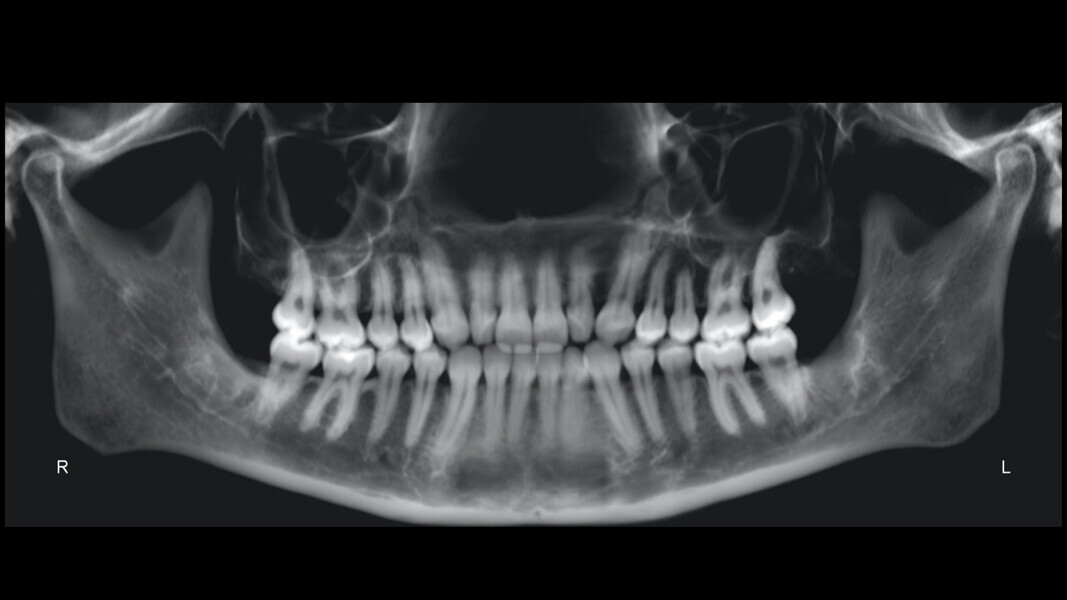

The final panoramic radiograph showed good root parallelism and confirmed that all treatment objectives had been met without root resorption or harm to periodontal health (Fig. 49). The final cephalometric radiograph and tracing confirmed the mandibular auto-rotation: a facial axis of 95° pretreatment to 97° post-treatment and an anterior facial height of 117.5 mm pretreatment to 115.9 mm post-treatment (Fig. 50).